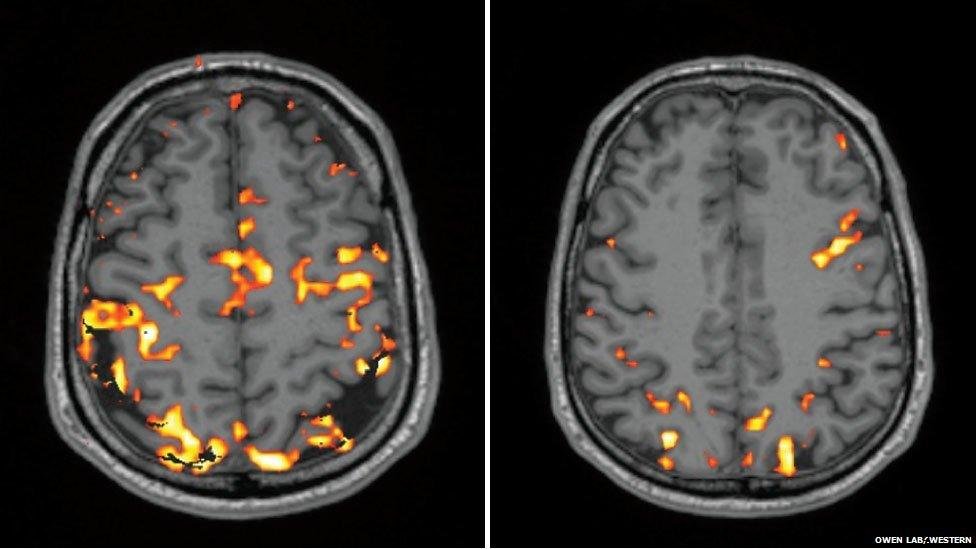

Visualize morning brain activity: Scans show increased prefrontal cortex engagement post-wake-up, key for Sudoku’s executive functions.

Evening brain scans reveal reduced frontal activity but sustained logic centers.